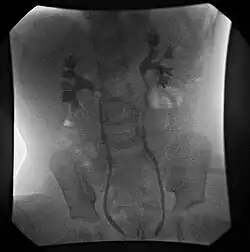

Wadę rozpoznaje się wykonując cystografię mikcyjną.

Wyróżniamy V stopni refluksu:

- Stopień I – cofający się mocz wypełnia tylko moczowód

- Stopień II – cofający się mocz wypełnia tylko moczowód, miedniczkę i kielichy nerkowe, nie powodując jednak ich poszerzenia

- Stopień III – stan jak wyżej, jednak dochodzi do poszerzenia miedniczek i kielichów nerkowych

- Stopień IV – umiarkowane poszerzenie moczowodu, możliwe też jest jego niewielkie zagięcie, całkowity zanik sklepień kielichów z zachowanym jednak zarysem brodawek

- Stopień V – znaczne poszerzenie moczowodu, staje się on poskręcany, zanik brodawek nerkowych w kielichach nerkowych.